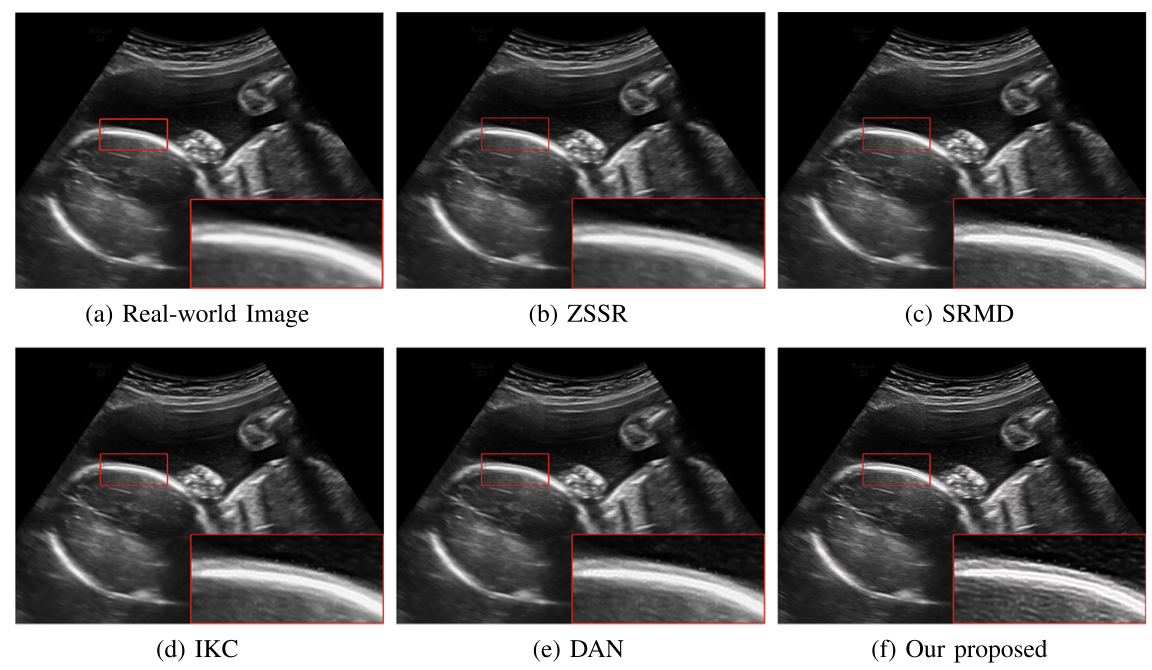

对于超声临床诊断而言,超声影像超分辨(ultrasound image super-resolution)可以提高超声成像质量,从而提高疾病诊断的准确性。但由于传感设备和传输介质的差异,实际场景中超声成像其退化模糊过程是未知且不可控的。为了解决未知退化场景超声医学影像准确超分辨的难题,团队提出了一种有效的基于退化模糊自估计且结合渐进残差学习和记忆提升机制的超声影像盲超分方法,初步实现了真实场景超声影像准确超分辨。相关研究成果发表在人工智能、计算机医学信息交叉领域一区TOP期刊《IEEE Journal of Biomedical and Health Informatics》(IF: 7.7)。公司为论文第一完成单位,TapTap点点刘恒教授、硕士生刘建勇分别为论文第一、第二作者。

(真实场景超声影像盲超分效果对比图)